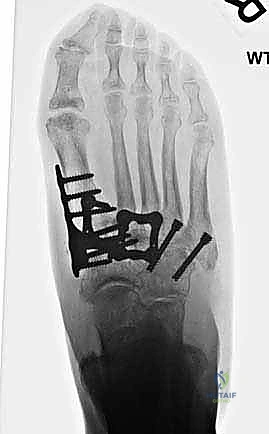

- الأشعة السينية أثناء الوقوف (Weight-bearing X-rays): وهي أهم أداة تشخيصية. الأشعة العادية والسرير فارغ لا تظهر المشكلة الحقيقية؛ يجب التقاط الأشعة والمريض يقف ليتحمل وزن الجسم، مما يظهر الانهيار الفعلي للمفاصل وتضيق المسافات بين العظام.

لضمان التحام العظام لتصبح عظمة واحدة صلبة، يجب تثبيتها بقوة هائلة حتى لا تتحرك أثناء فترة الشفاء. يتم استخدام مسامير معدنية متطورة (Screws)، أو شرائح معدنية خاصة (Plates)، أو دبابيس طبية متخصصة (Staples) مصنوعة من التيتانيوم الآمن على الجسم.

بعد التأكد التام من وضع العظام وثباتها باستخدام جهاز الأشعة السينية داخل غرفة العمليات (C-Arm)، يتم إغلاق الشقوق الج